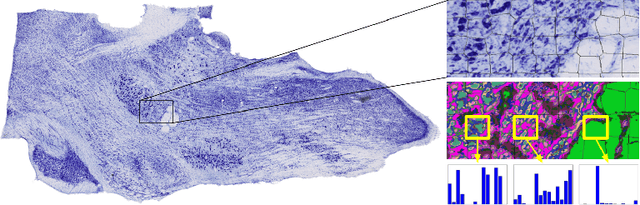

Brightfield and fluorescent imaging of whole brain sections are funda- mental tools of research in mouse brain study. As sectioning and imaging become more efficient, there is an increasing need to automate the post-processing of sec- tions for alignment and three dimensional visualization. There is a further need to facilitate the development of a digital atlas, i.e. a brain-wide map annotated with cell type and tract tracing data, which would allow the automatic registra- tion of images stacks to a common coordinate system. Currently, registration of slices requires manual identification of landmarks. In this work we describe the first steps in developing a semi-automated system to construct a histology at- las of mouse brainstem that combines atlas-guided annotation, landmark-based registration and atlas generation in an iterative framework. We describe an unsu- pervised approach for identifying and matching region and boundary landmarks, based on modelling texture. Experiments show that the detected landmarks corre- spond well with brain structures, and matching is robust under distortion. These results will serve as the basis for registration and atlas building.